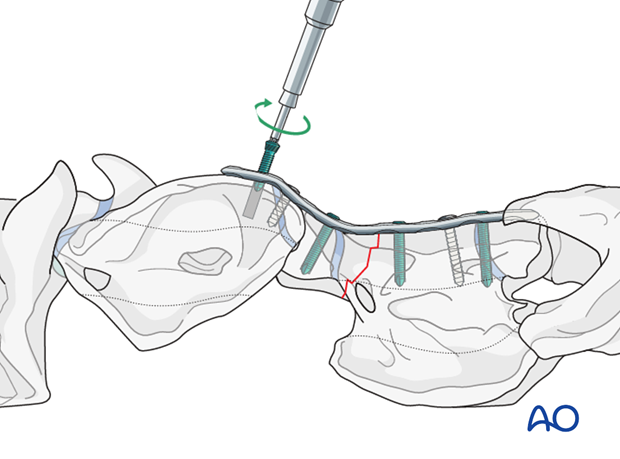

The use of the locking compression plate (LCP) is preferred for fracture fixation of the vertebrae. According to the size of the patient, a small or broad 3.5/4.0 or 4.5/5.0mm LCP are used.

Alternatively, a human distal femur plate can be used to improve the stabilization of the atlas when an atlantoaxial arthrodesis is intended.

Minimal plate bending is needed.

With the reduction forceps in position, the appropriately sized plate is applied to the ventral aspect of C1 and C2.

One cortex screw is inserted into each fragment in loaded fashion. The correct length of the screws is determined with the help of fluoroscopy.

Note: Attention must be paid not to damage the spinal cord.

The remaining holes are filled with locking screws.